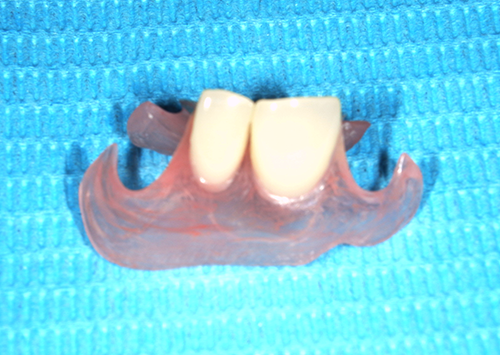

コンフォート義歯は金属の代わりに特殊なアクリル樹脂(ポリカーボテート)を使用しています。

隣の歯に負担をかけない、床の内側に軟かいシリコンが敷き詰めてあり、強く噛んでも痛みが出にくいというメリットがあります。

また口元が自然に見えて、若々しくなります。

実際にKIさん専用に作成したコンフォート義歯はこちら↓

KIさんが装着したコンフォート義歯はこちらです。